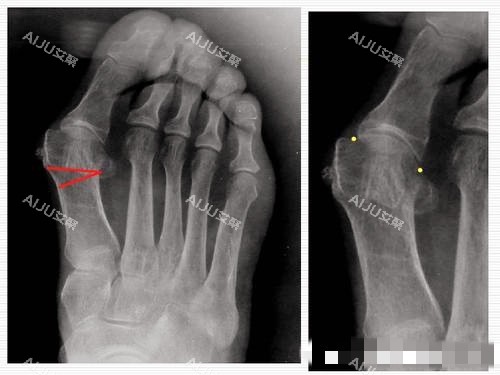

大脚骨,医学上称为拇外翻,是一种常见的足部畸形问题。

它不仅影响脚部的美观,还会导致疼痛、行走不便等问题,严峻影响患者的生活质量。